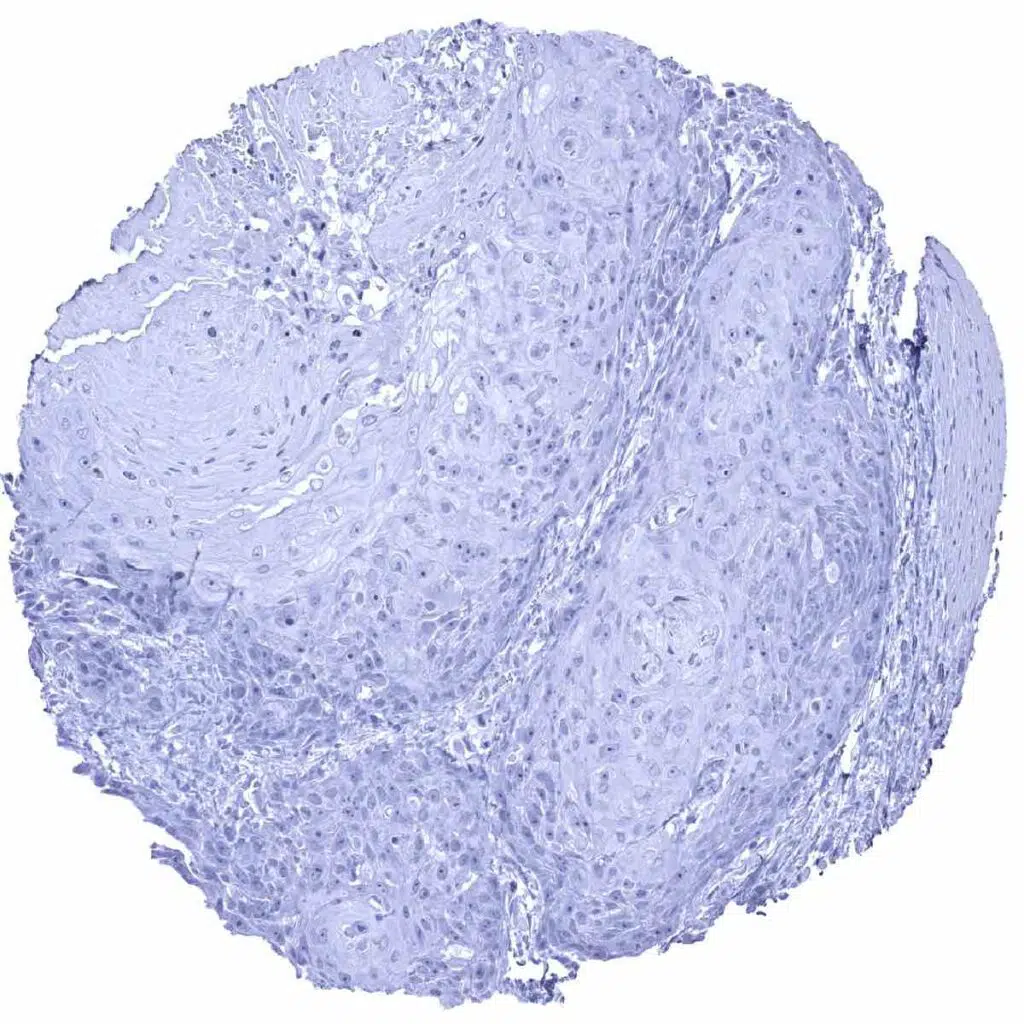

Oral cavity - Squamous cell carcinoma without any CD23 positive cells